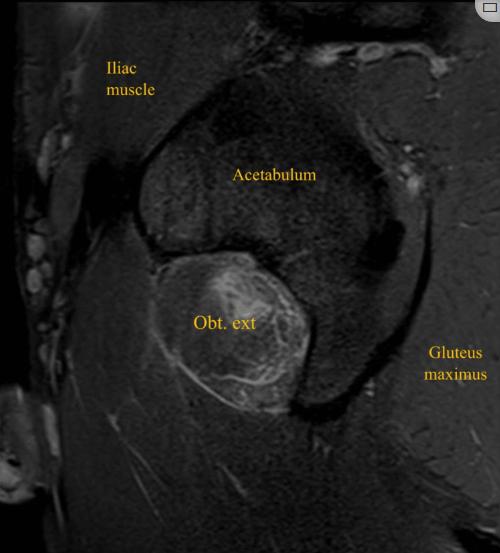

患者男性,32岁,职业足球运动员,在赛季训练期间出现急性左腹股沟疼痛和臀部疼痛,视觉模拟量表(VAS)评分为8/10,这是由髋关节的快速和负重内旋运动引起的,髋关节和膝关节弯曲约90度,在快速改变方向和切入进攻的过程中,功能立即丧失。患者否认腿部有任何麻木、虚弱或辐射性疼痛。体检时,没有瘀伤、瘀斑、水肿或肿胀。坐骨结节触诊有轻微疼痛和压痛。在内收肌、腘绳肌或髂腰肌的特定测试中未发现异常。膝关节和髋关节处于90°时髋关节主动外旋和被动内旋都会引起髋关节疼痛。这位运动员跛行。对左髋关节进行x线检查,以排除髋关节病变,包括股骨髋臼撞击。核磁共振成像显示左侧闭孔外肌的后腱膜下/肌腱膜撕裂,从耻骨起点延伸至外侧肌腱连接处,横断面测量为10 cm,前后径为3.5 cm,伴有股方肌和闭孔内肌间质水肿(图1-4)。

图4、左大腿 (STIR) MRI显示左闭孔外撕裂